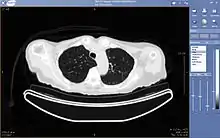

A picture archiving and communication system (PACS) is a medical imaging technology which provides economical storage and convenient access to images from multiple modalities (source machine types).[1] Electronic images and reports are transmitted digitally via PACS; this eliminates the need to manually file, retrieve, or transport film jackets, the folders used to store and protect X-ray film. The universal format for PACS image storage and transfer is DICOM (Digital Imaging and Communications in Medicine). Non-image data, such as scanned documents, may be incorporated using consumer industry standard formats like PDF (Portable Document Format), once encapsulated in DICOM. A PACS consists of four major components: The imaging modalities such as X-ray plain film (PF), computed tomography (CT) and magnetic resonance imaging (MRI), a secured network for the transmission of patient information, workstations for interpreting and reviewing images, and archives for the storage and retrieval of images and reports. Combined with available and emerging web technology, PACS has the ability to deliver timely and efficient access to images, interpretations, and related data. PACS reduces the physical and time barriers associated with traditional film-based image retrieval, distribution, and display.

The architecture is the physical implementation of required functionality, or what one sees from the outside. There are different views, depending on the user. A radiologist typically sees a viewing station, a technologist a QA workstation, while a PACS administrator might spend most of their time in the climate-controlled computer room. The composite view is rather different for the various vendors.[2]

Typically a PACS consists of a multitude of devices. The first step in typical PACS systems is the modality. Modalities are typically computed tomography (CT), ultrasound, nuclear medicine, positron emission tomography (PET), and magnetic resonance imaging (MRI). Depending on the facility's workflow most modalities send to a quality assurance (QA) workstation or sometimes called a PACS gateway. The QA workstation is a checkpoint to make sure patient demographics are correct as well as other important attributes of a study. If the study information is correct the images are passed to the archive for storage. The central storage device (archive) stores images and in some cases reports, measurements and other information that resides with the images. The next step in the PACS workflow is the reading workstations. The reading workstation is where the radiologist reviews the patient's study and formulates their diagnosis. Normally tied to the reading workstation is a reporting package that assists the radiologist with dictating the final report. Reporting software is optional and there are various ways in which doctors prefer to dictate their report. Ancillary to the workflow mentioned, there is normally CD/DVD authoring software used to burn patient studies for distribution to patients or referring physicians. The diagram above shows a typical workflow in most imaging centers and hospitals. Note that this section does not cover integration to a Radiology Information System, Hospital Information System and other such front-end system that relates to the PACS workflow.